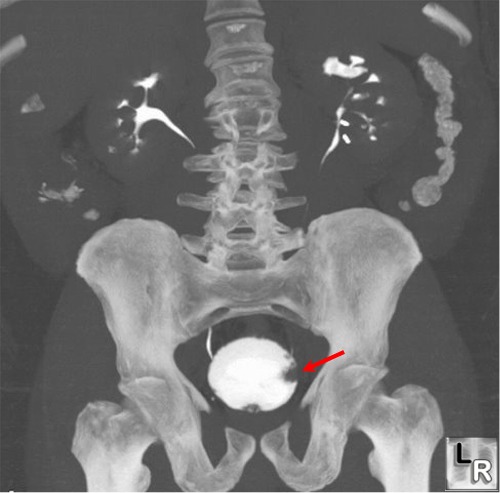

Enhanced MRI showing a bladder tumor at the left wall (arrow). Arrow…

CT scan showing the location of bladder tumor. | Download Scientific …

Urothelial carcinoma of the bladder in a 59-year-old man. CT image …

CT scan of Case 1: bladder cancer mass with associated left …

CT scan showing bladder wall thickening (arrow) and decrease in tumor …